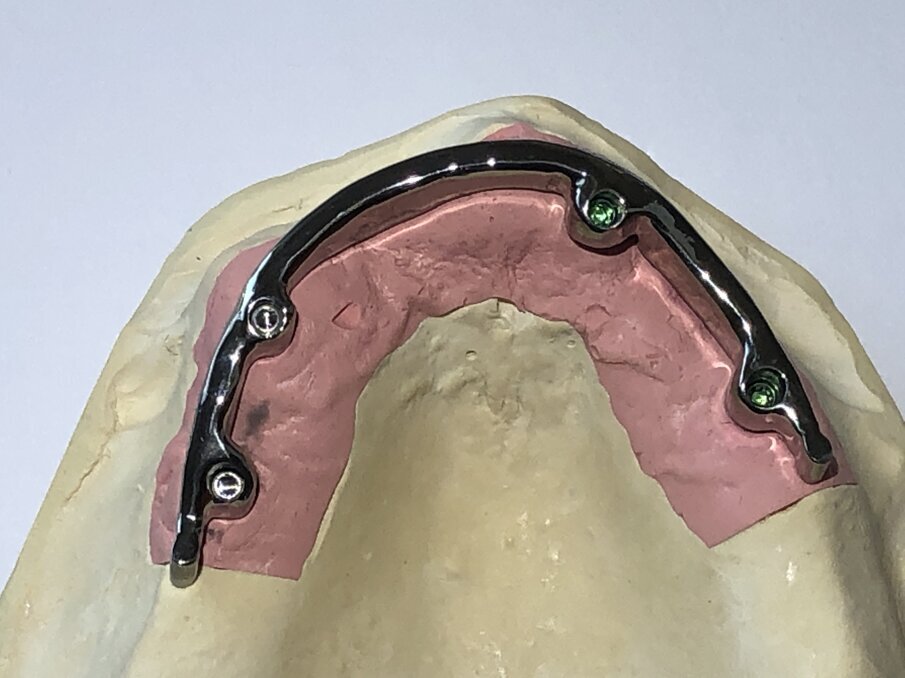

Een andere staafconstructie is de individueel handmatig gefreesde staafconstructie. Een identiek secundair deel van metaal is bevestigd in de prothese en verankerd met behulp van één of twee precisie-kunststoffen-onderdelen (afbeelding 8, 9 en 10, de groene delen).